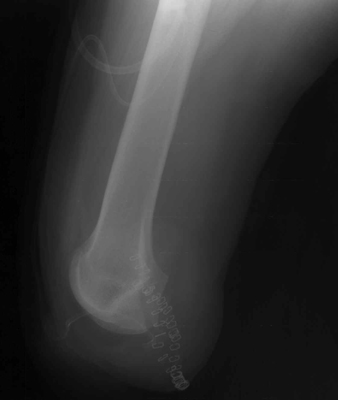

The knee disarticulation

results in an excellent weight-bearing stump. It is most often used in children and

young adults, but is nearly always avoided in the elderly and patient with ischemic

disease. Several advantages of the knee disarticulation include: 1) a

large end surface covered by skin and soft tissues that is naturally suited for weight

bearing; 2) a long lever arm controlled by strong muscles; 3)

increased stability of the patients prosthesis. A main disadvantage of the knee

disarticulation is cosmetic. The patient's prosthetic leg will have a knee that

extends far beyond his own knee in the sitting position. This tends to leave the

portion of the prosthesis below the knee dangling off the floor when the patient sits.

The image shown demonstrates an immediate post-operative knee disarticulation.